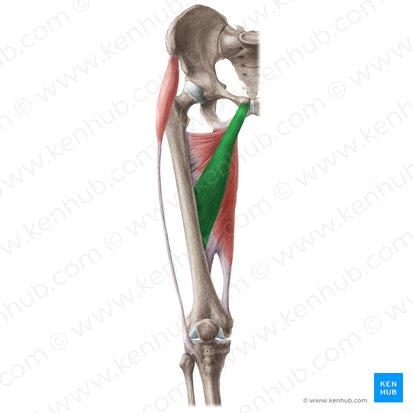

adductor brevis

O: inferior ramus of pubis

I: linea aspera

A: adducts thigh

N: obturator nerve